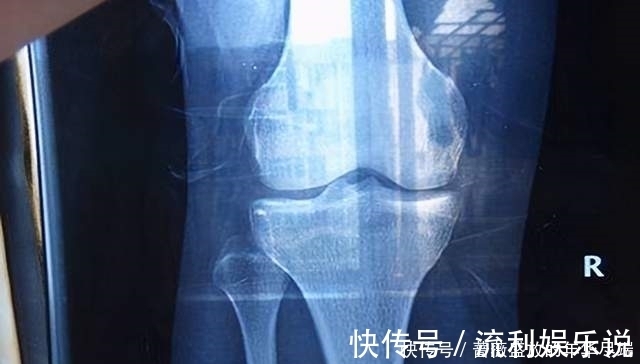

因为人的骨骼发育需要钙,而性早熟的孩子钙储备并不多,并且性早熟会加速骨骼骨骺线闭合,所以孩子会暂停长个。